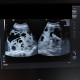

ALO Dokter, Pasien saya perempuan usia 45 tahun datang ke IGD dengan keluhan nyeri perut dan perdarahan abnormal selama 3 minggu terakhir. Pada saat saya lakukan pemeriksaan USG, saya menemukan gambaran ini pada daerah uterus dan ovarium. Apakah dapat kita curigai sebagai keganasan dok?

Melihat gambaran usg didaerah pelvic mengarah ke solid mass dengan cystic area disertai papil mass. Dengan usia 45 tahun perlu dicurigai suatu keganasan . Bagaimana dengan pemeriksaan inspekuko di area cerviks , perlu di pastikan apakah ada patologi di area tersebut.